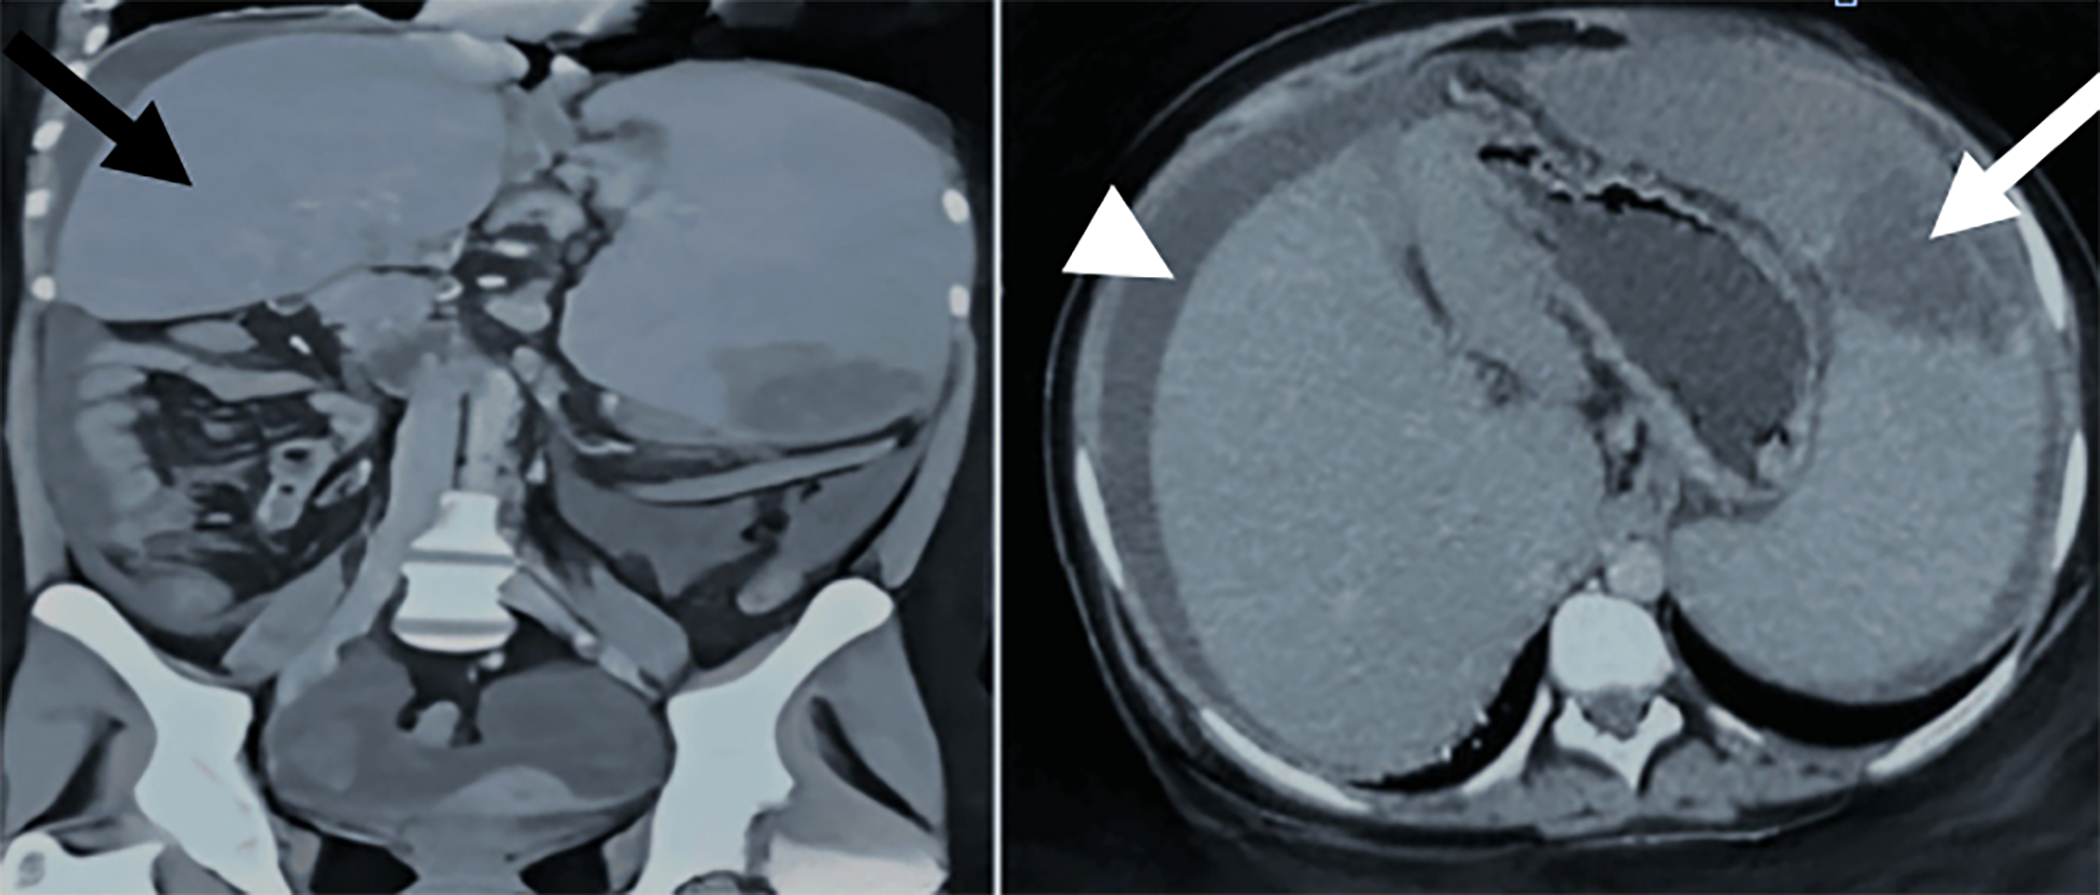

A 16-year female, resident of Sindh, presented with excruciating abdominal pain and fever of 102-103˚F for a month. The abdomen was distended with a palpable, tender spleen, crossing the midline. Ultrasound of the abdomen showed a massively enlarged spleen with infarctions and moderate ascites. These findings were further confirmed by contrast- enhanced computed tomography (CECT) abdomen, with the addition of splenic vein thrombosis (Figure 1). She was worked-up meticulously at the age of 7 years, with upper gastrointestinal (UGI) endoscopy and bone marrow biopsy, which were unremarkable.

Figure 1: Contrast-enhanced CT of abdomen. Left-coronal section - healthy liver tissue (black arrow). Right-transverse section-wedged shaped area of infarction in the spleen (white arrow) and ascites (white arrow head).